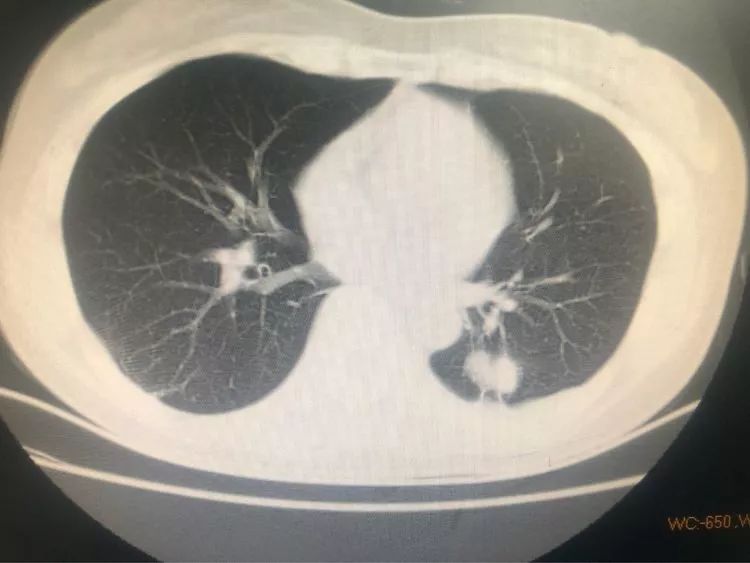

第二例 46岁的刘阿姨既往有肺结核病史,规则治疗,三月前出现胸背部隐痛,在其他医院胸片检查考虑陈旧性结核,但她一直未在意,之后由于症状一直没有缓解便选择来省胸科医院就诊,经检查,胸部CT两上肺确实有陈旧性病兆,但左下背段有一个1.5厘米左右的结节。

像这种肺外周的结节一般的气管镜做不到,所以医生选择使用穿刺活检。

穿刺活检后送至病理科,待报告出来后显示腺癌,可惜,癌细胞已经向肋骨和胸椎多处转移,患者已经失去了手术机会。